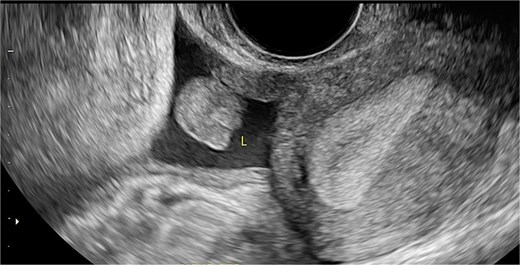

Stage III pelvic inflammatory disease (PID) was suspected based on ultrasound (Figs 1–3) and gynecological examination, which revealed mild bulging of the right lateral fornix, cervical motion tenderness, and a white, non-foul-smelling vaginal discharge. Empiric intravenous antibiotic therapy was initiated, followed by exploratory laparotomy via a Pfannenstiel incision. Intraoperative findings included an 8 × 5 cm uterus, edematous fallopian tubes, and a simple 5 × 5 cm left adnexal cyst. Cystectomy was performed.

Sagittal transvaginal ultrasound showing free fluid in the uterine fundus.